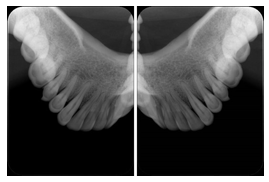

2 Occlusal Vertical Maxilla A Dental Image Layout

DL-C001A

Reference: DL-C001-U1L0

Reference: DL-C001-U2L0

00

Occlusal

18, 17, 16, 15, 14, 13, 12, 11, 13, 12, 11

01

21, 22, 23, 24, 25, 26,27, 28

2 Occlusal Vertical Mandible A Dental Image Layout

DL-C002A

Reference: DL-C002-U0L1

Reference: DL-C002A-U0L2

10

48, 48, 47, 46, 45, 44, 43, 42, 41

11

31, 32, 33, 34, 35, 36, 37, 38

2 Occlusal Horizontal Maxilla A Dental Image Layout

DL-C003A

Reference: DL-C003-U1L0

Reference: DL-C003-U2L0

18, 17, 16, 15, 14, 13, 12, 11, 13, 12, 11, 21, 22, 23, 24, 25, 26,27, 28

2 Occlusal Horizontal Mandible A Dental Image Layout

DL-C004A

Reference: DL-C004-U0L1

Reference: DL-C004-U0L2

48, 48, 47, 46, 45, 44, 43, 42, 41, 31, 32, 33, 34, 35, 36, 37, 38